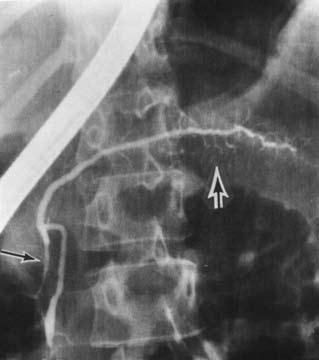

Контрастное исследование желчных путей (холангиография) необходимо, в первую очередь, больным с билиарным ХП или подозрением на таковой. Она осуществляется либо непрямым методом с пероральным или внутривенным введением контрастного вещества, который, к сожалению, не обеспечивает достаточное качество снимков и вообще неприменим у больных с обтурацией желчных путей, либо методом прямого контрастирования. Последнее достигается при уже упоминавшейся РХПГ, а также с помощью чрескожной чреспеченочной пункции желчного пузыря, в том числе под контролем УЗИ, КТ или лапароскопа (рис. 133).

Рис. 133. Ретроградная холангиопанкреа-тография. Контрастированы желчные протоки и желчный пузырь и главный панкреатический проток. Имеется продленное сужение (симптом "мышиного хвостика") терминального отдела общего желчного протока (панкреатическая часть) и резкое расширение главного панкреатического протока с нечеткостью его контуров

На одновременно осуществляемой холангиограмме может выявляться стриктура терминальной части холедоха, расширение вне-и внутрипеченочных желчных протоков, холедохолитиаз и т. д. Учитывая возможные осложнения РХПГ (острый панкреатит, острый холангит вплоть до развития бактериально-септического шока при наличии инфекции в протоках до РХПГ), это исследование выполняется в основном по абсолютным показаниям, перед операцией или с одновременной эндоскопической декомпрессией протоков.